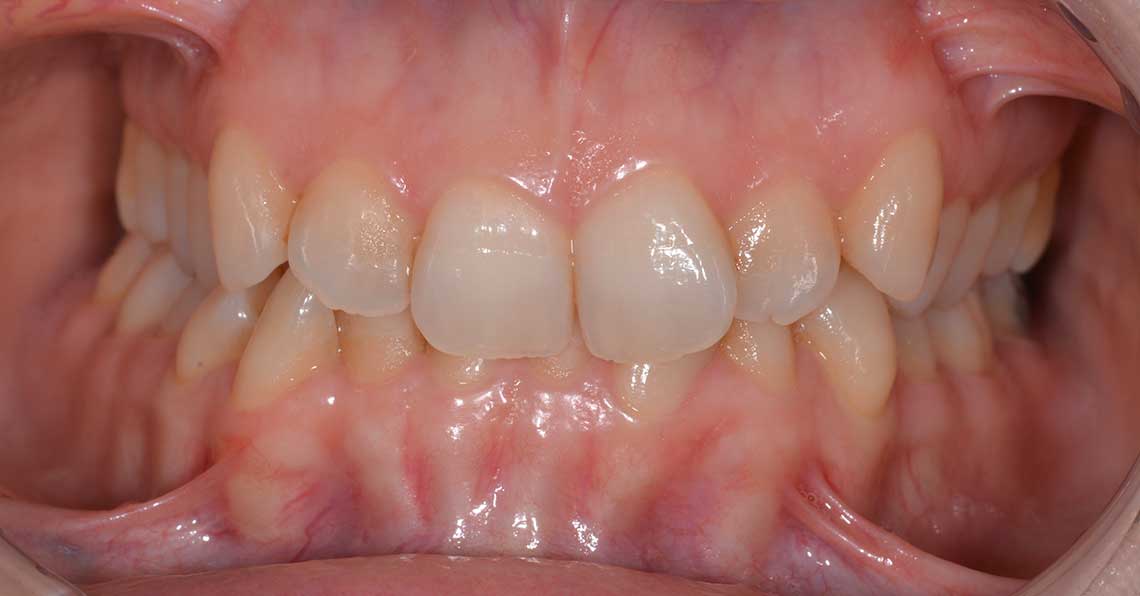

Ortodonzia allineatori – caso clinico 1